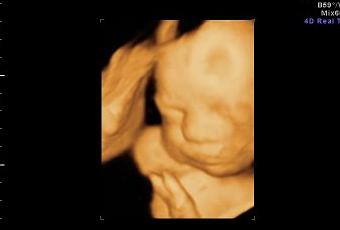

Ahora Marisa, “supuestamente”, está haciendo reposo. La última ecografía, esta vez en 4D, muestra que todo va bien. El niño pesa unos 1200 gramos y debería llegar hasta los 3 Kg en las semanas que quedan. En teoría saldríamos de cuentas para mediados de Enero. Pero Diego ya ha dado amagos de querer venir antes en varias ocasiones. Parece estar deseoso de empezar a entrenar Karate.